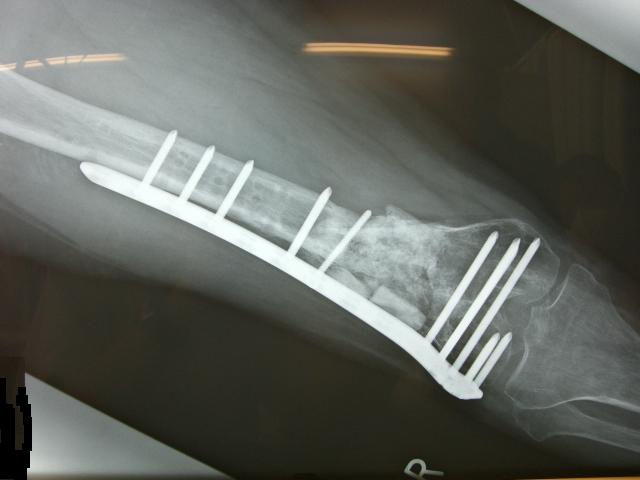

¥ê¥Ï¥Ó¥ê

º£¤Þ¤ÇËͤα¦Â­¤Ë¤ÏÁõ¶ñ¤¬ÉÕ¤¤¤Æ¤¤¤Þ¤·¤¿¡£

¤³¤ÎÁ°¤Î¿Ç»¡¤Ç¤«¤Ê¤ê¤¤¤¤´¶¤¸¤Ë¹ü¤¬½ÐÍè¤Æ¤¤¤¿¤Î¤Ç

Áõ¶ñ»×¤¤Î©¤Ã¤¿¤¬µÈÆü¤Ç

º£Æü¤«¤é¤³¤ÎÁõ¶ñ¤ò³°¤·¤Æ

Êâ¹Ô·±Îý¤Ç¤¹¡£

ºÇ½é¤ÏÉݤ¯¤Æ¡¢À¸¤Þ¤ì¤¿¤Æ¤Î»Ò¼¯ÍͤË

Ê⤭½Ð¤»¤Ê¤«¤Ã¤¿¤±¤É¡¢»þ´Ö¤ò³Ý¤±¤Æ¤æ¤Ã¤¯¤êÊ⤯Îý½¬¤ò¤·¤Þ¤·¤¿¡£

°ÊÁ°¤«¤éDr¤ËÁõ¶ñ¤ò³°¤·¤ÆÊ⤯Îý½¬¤ò¤¹¤ë¤è¤¦»Ø¼¨¤µ¤ì¤Æ¤¤¤¿¤ó¤Ç¤¹¤¬

¤È¤Æ¤âÉݤ¯¤Æ³°¤»¤Þ¤»¤ó¤Ç¤·¤¿¤¬¡¢¤â¤¦¹ü¤â·Ò¤¬¤Ã¤Æµï¤ë»ö¤Ê¤Î¤Ç

²¿¤È¤«´èÄ¥¤Ã¤Æ¤ß¤¿¤è¡£

¥¢¥ë¥×¥¹¤Î¾¯½÷¥Ï¥¤¥¸¤Ë½Ð¤Æ¤¯¤ë¥¯¥é¥é¤Îµ¤»ý¤Á¤¬¾¯¤·Ê¬¤ê¤Þ¤·¤¿¡£

°ìÉô¤Ç¤Ï¤¢¤ëʪ¤Îº£¤Þ¤ÇÎ¥¤ì¤Æ¤¤¤¿

ÂçÂܹü¤¬¸«»ö¤Ë°ìËܤιü¤Ë¡ª

¸«¤è¡ª¤ï¤¬¿È¤òÄ褷¤ÆÂ©»Ò¤Î°Õ¸«¤ò

¾ÚÌÀ¤¹¤ë¸¥¿ÈŪ¤ÊÉã¿Æ¤Î»Ñ¡ª

¼ã´³·ä´Ö¤Ï¤¢¤ë¤Î¤Ç¤¹¤¬¡¢½çÄ´¤Ë²óÉü¤Ë¸þ¤«¤Ã¤Æ¤Þ¤¹¡£